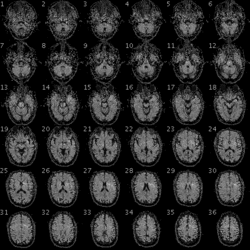

![]() An fMRI image with yellow areas showing increased activity compared with a control condition | |

| Purpose | Measures brain activity detecting changes due to blood flow. |

Functional magnetic resonance imaging or functional MRI (fMRI) measures brain activity by detecting changes associated with blood flow.[1][2] This technique relies on the fact that cerebral blood flow and neuronal activation are coupled. When an area of the brain is in use, blood flow to that region also increases.[3]